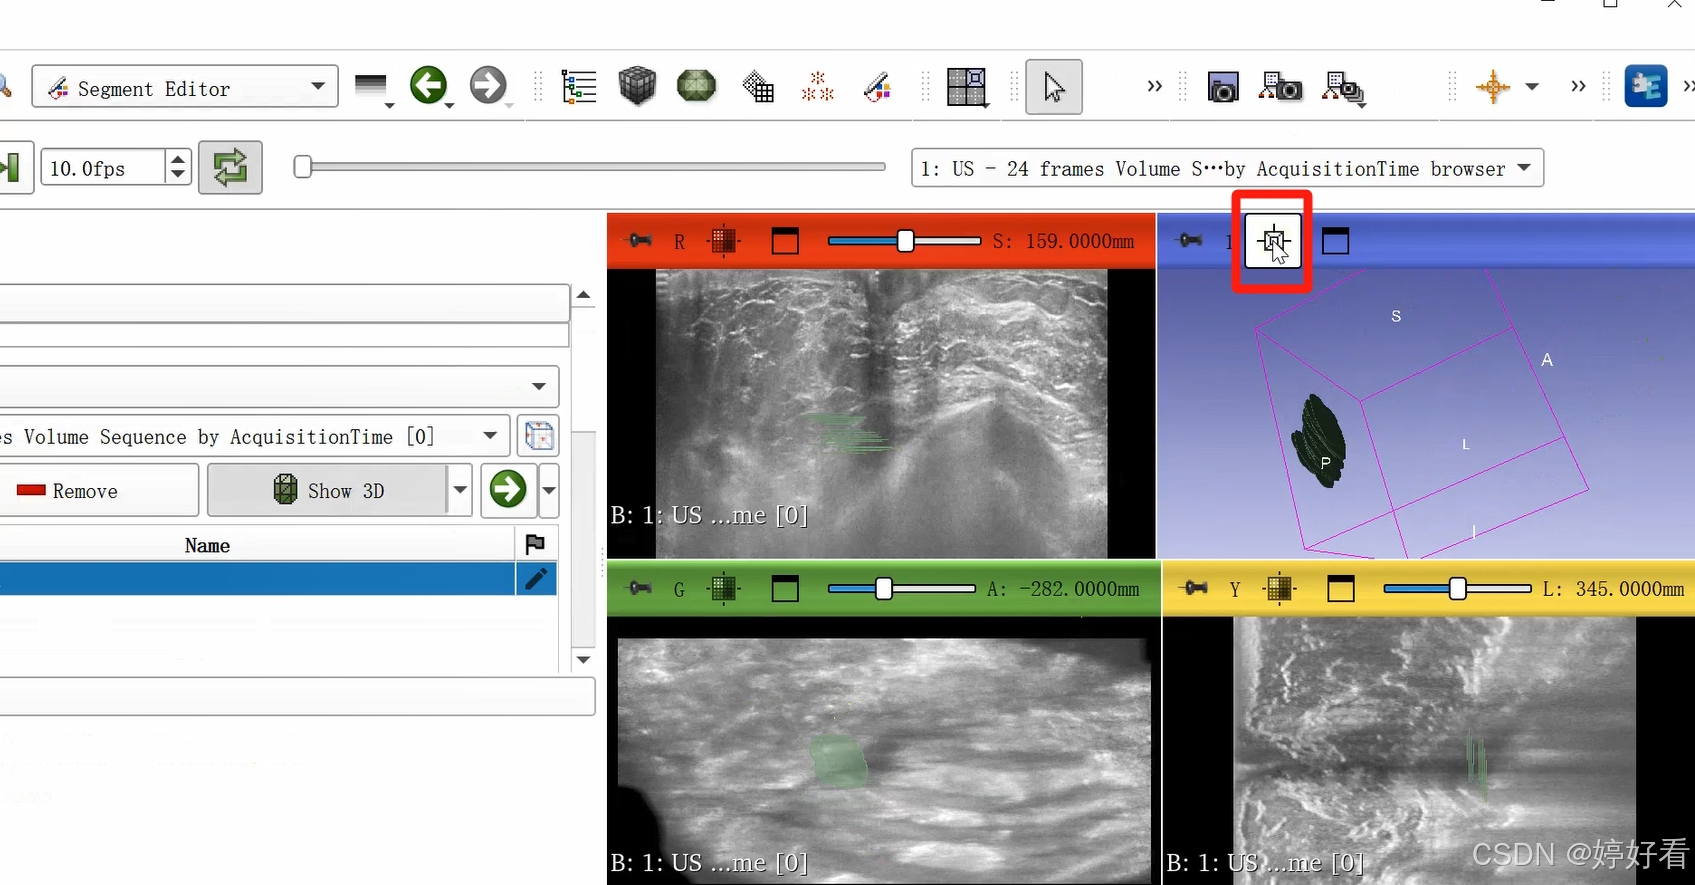

2.5 选中以下居中的符号,使绘制好的三维图像居中。